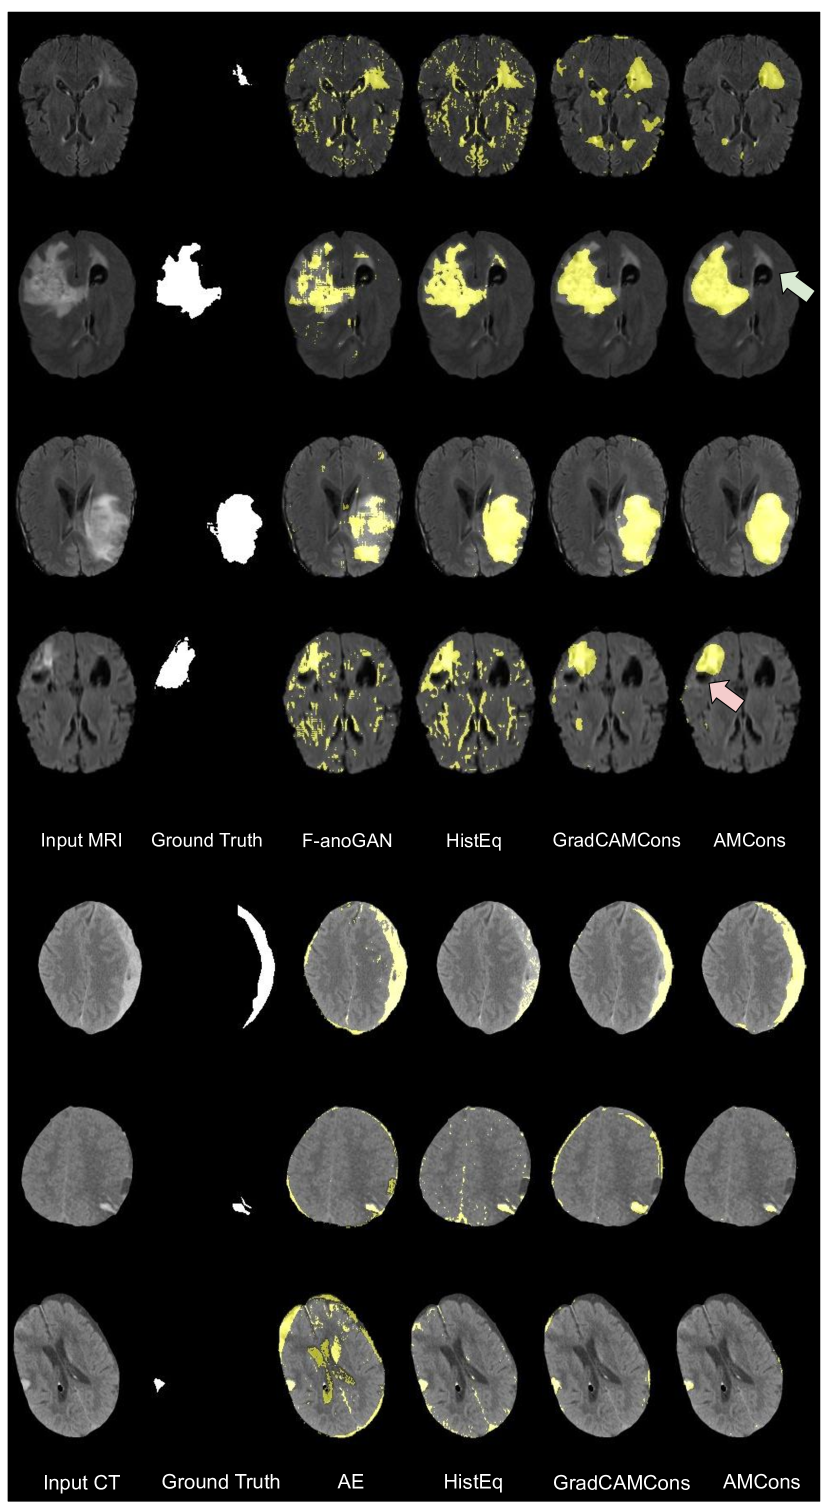

5.4 Qualitative evaluation

Visual results of the proposed and existing methods for both datasets are depicted in Figure 8. We can observe that our approach identifies as anomalous more complete regions of the lesions, whereas existing methods are prone to produce a significant amount of false positives (first, third and seventh rows) and fail to discover many abnormal pixels (third row). These visual results are in line with the quantitative validation performed in previous sections. However, there is a known problem about segmenting only hyperintense regions in the state-of-the-art methods of unsupervised anomaly localization of brain lesions ([31]). Although the proposed method still suffers from this limitation (fourth row, red arrow), the positive results regarding true negative segmentation obtained in some normal, hyperintense tissue (second row, green arrow) suggest an improvement in relation to this problem.